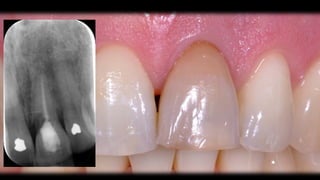

Patient 2

* male

* 35 years

* patient’s request:

- solution for discoloured

central incisor (21)

periodontal chart

buccal recession 11 and 21

21 internal root resorption, discoloured